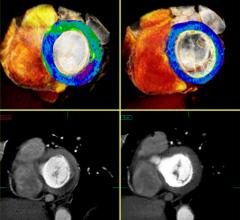

Angiography, Computed Tomography (CT), Flat Panel Displays, Information Technology, Magnetic Resonance Imaging (MRI), Mobile C-Arms, Nuclear Imaging, Ultrasound Imaging

With headquarters in Tustin, Calif., Canon Medical Systems USA Inc. markets, sells, distributes and services radiology and cardiovascular systems, and coordinates clinical diagnostic imaging research for all modalities in the United States. Canon Medical Systems Corporation, an independent group company of Canon Inc., is a global leading provider of diagnostic imaging systems including CT, MRI, Ultrasound, X-ray systems and clinical laboratory systems. In business for more than 100 years, Canon Medical Systems Corporation (formerly Toshiba Medical Systems Corp.) was built to improve the quality of life for all people. It delivered on this mission with medical innovations that are “Made for Life”—made to improve the lives of patients, clinicians and administrators. Its legacy was built with pioneering medical technology, such as the world's first X-ray machines in 1932 and Japan's first magnetic resonance imaging (MRI) systems in 1983. Canon Inc. entered the healthcare business in 1940 with the development of Japan’s first indirect X-ray camera which was used for the early detection of pulmonary tuberculosis. The partnership of Toshiba Medical Systems Corporation and Canon (now Canon Medical Systems Corp.) brings together two cutting-edge technology businesses, founded with similar values of creativity, flexibility and patient-friendly healthcare solutions. Today, their combined history of research and innovation drive forward Canon Medical Systems’ vision for building a world-class healthcare enterprise. For more information: https://us.medical.canon/

Canon Medical Systems’ offering includes: computed tomography, magnetic resonance, ultrasound, X-ray, cath and EP lab